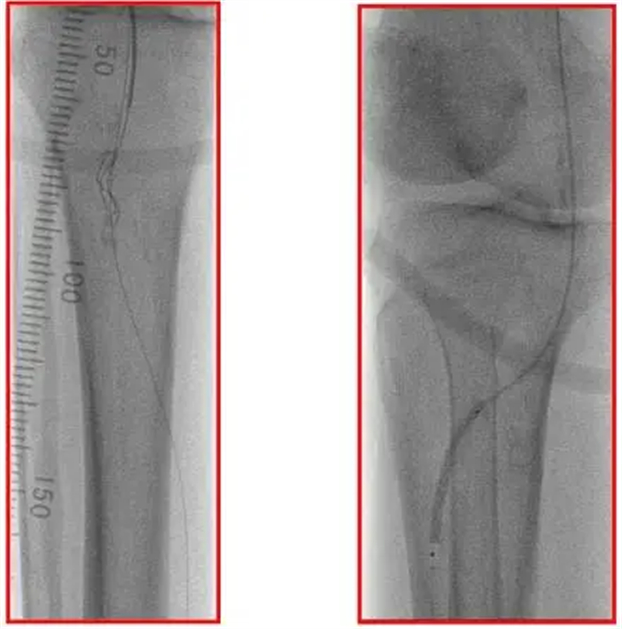

导丝通过,冲击波球囊扩张

考虑到患者血管钙化程度重、膝下血管管径细(约2.5mm),传统治疗效果有限,外科团队决定采用冲击波球囊介入治疗。手术中,医生通过微创方式将直径匹配的冲击波球囊送至钙化病变处,球囊膨胀后释放低频、低能量冲击波——这种冲击波能精准作用于坚硬的钙化斑块,将其 “击碎” 却不损伤血管壁。

术中造影显示,原本狭窄的血管管腔瞬间恢复通畅,血流即刻灌注至足趾末端,狭窄率降至 10% 以下,且无需植入支架,最大程度保留了血管自身结构。